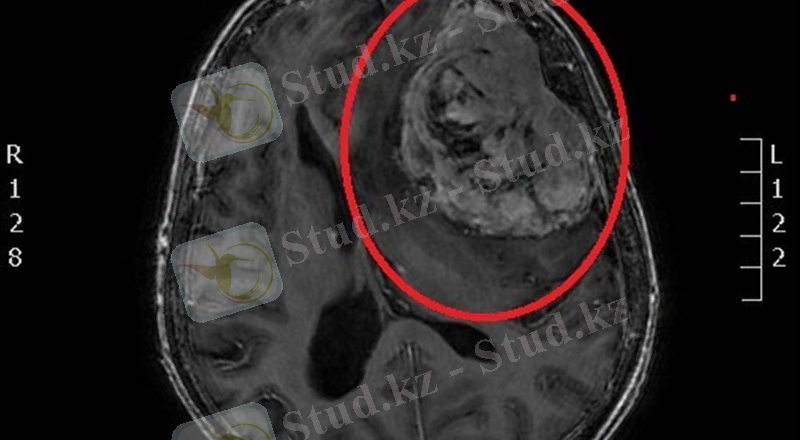

Жүйке жүйесінің ісіктері.

Қатерсіз астроцитома иттерде көп кездеседі. Ол мишықта, ми бағанында түйін түрінде өседі. Арасында киста пайда болады. Қатерлі астроцитома клетка полиморфизімен сипатталады. Ісікте некроз ошақтары кездеседі.

М енингиомалар немесе арахноидэндоте-лиомалар деп аталады. Ісік қатты түйін түрінде өсіп, мидың қатты қабығынан немесе жұмсақ қабаттарын астарлап жатқан арахноидэндотелий клеткаларынан өседі. Оның мына түрлерін ажыратады: а) Менинготелиалдық менингиома -майда, цитоплазмасы ашық түсті, ядросы сопақша, хроматині әлсіз боялған клеткалардан тұрады; ә) Қат-қабат құрылымды менингиома -қабаттанып бір-біріне айнала орна-ласқан; б) Ангиоматоздық менингиома құрамында қан тамырлары көп; в) Фиброз-дық менингиомада клеткалар әртүрлі бағытта орналасқан будалар түзеді.

Олигодендроглиалық ісіктер. Ол негізінен аралары өте жақын, ядросы ірі, домалақ, ал ядро айналасында түссіз аймағы бар клеткалардан түзіледі.